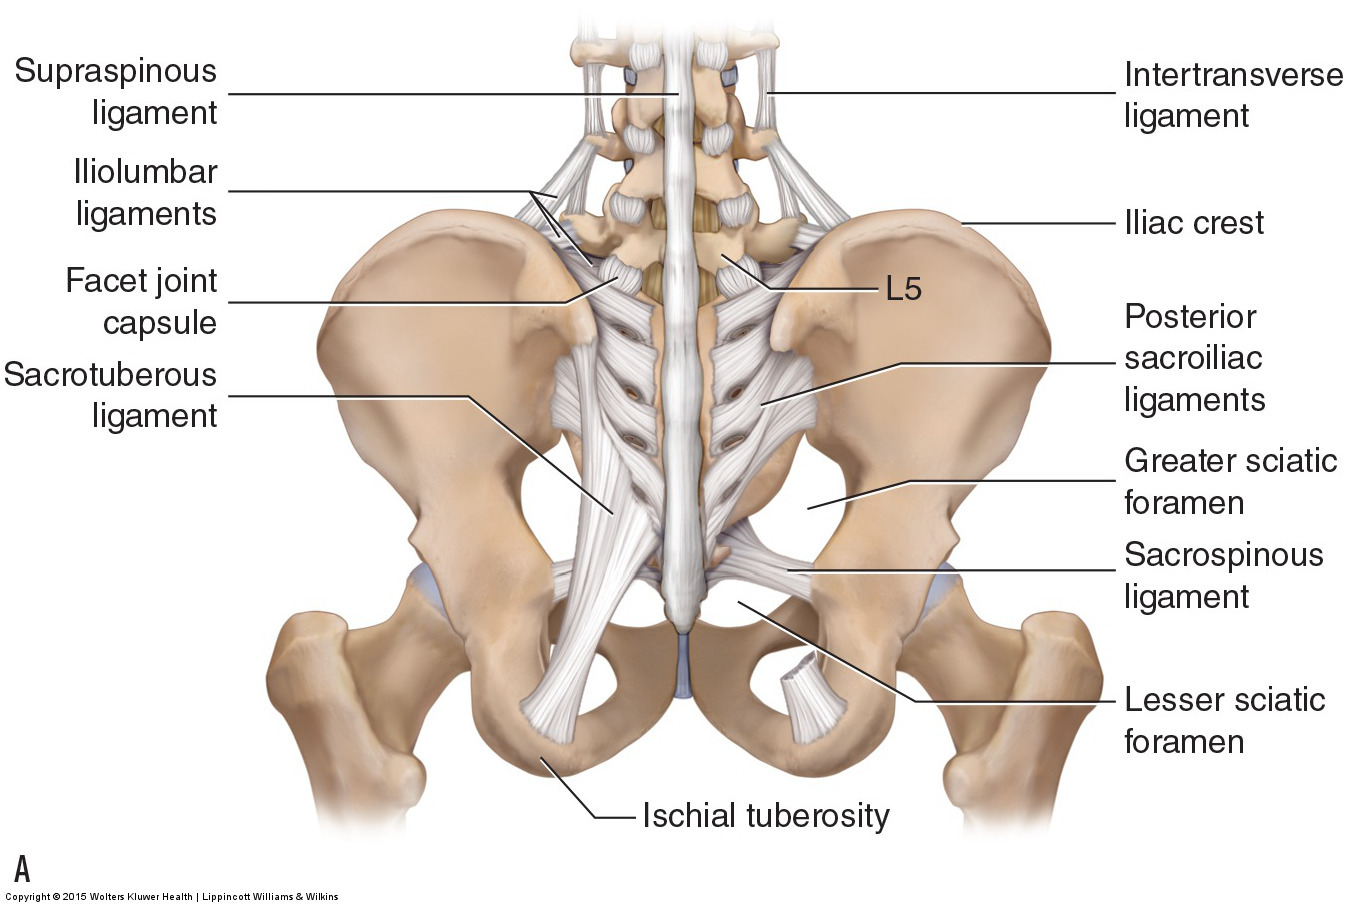

Pure Health - Anatomy 101 - Supraspinous ligament and interspinous ligament 📚 The supraspinous ligament and interspinous ligament work together to limit flexion of the spine by limiting separation of the spinous

DOCS - The interspinous ligament is located between the spinous processes of adjacent vertebrae in the spine. It extends from the base of one spinous process to the apex of the next,